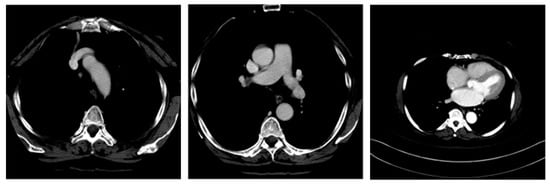

The medical images for this study required pre-label metadata for training purposes, so the images were collected from a trustworthy source. For this purpose, about 1700 pre-labeled CT images were retrieved from the National Institute of Health (NIH) medical image database, the DeepLesion [18]. Examples of these images are shown below in Figure 3.

Figure 3.

Example of pre-labeled CT images from DeepLesion.